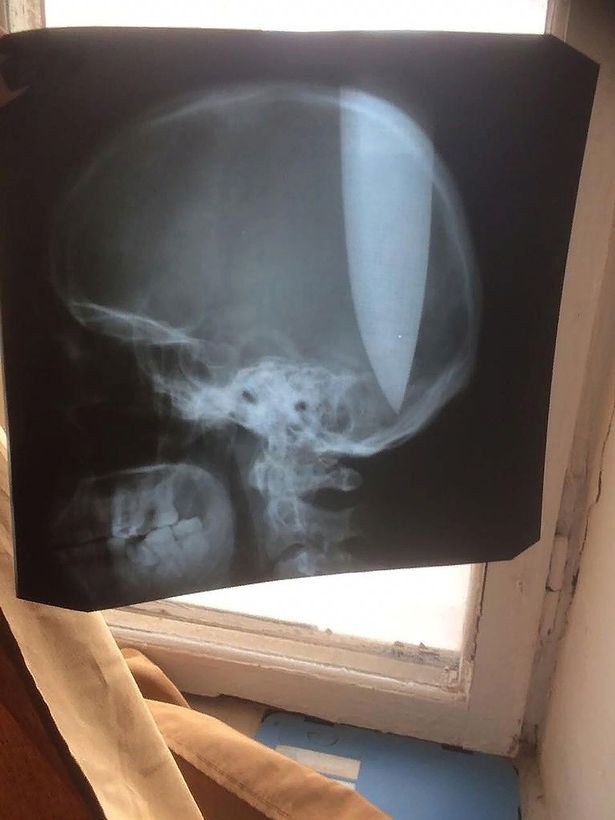

Ảnh chụp X-quang tình trạng của Zhokhov.

Ảnh chụp X-quang cho thấy con dao đâm sâu vào não Zhokhov. Các bác sĩ nói việc người đàn ông này còn tỉnh táo hay không bị tổn thương nghiêm trọng là điều “thần kỳ”.